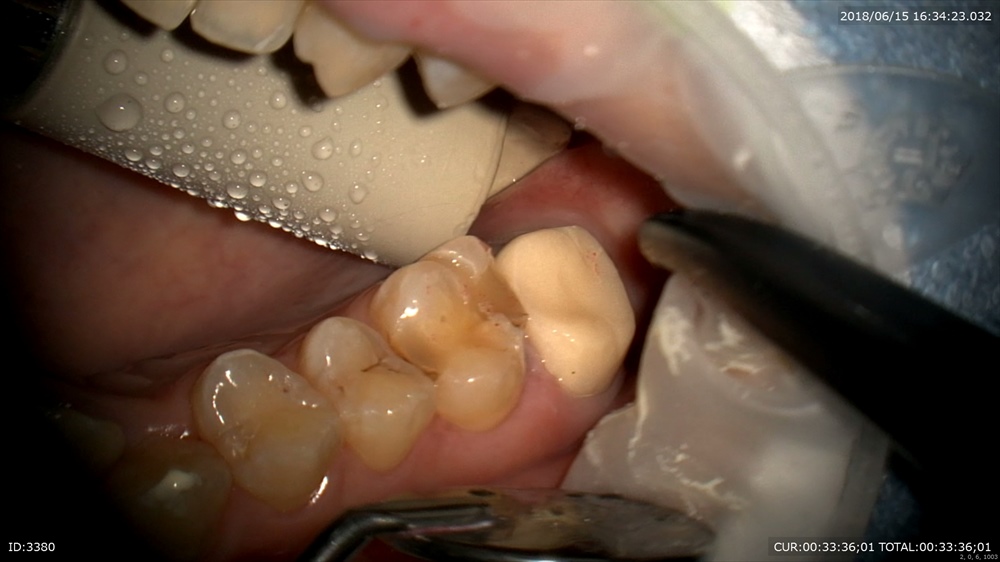

ですので本日土台と仮歯を入れました。

土台。

仮歯

セット